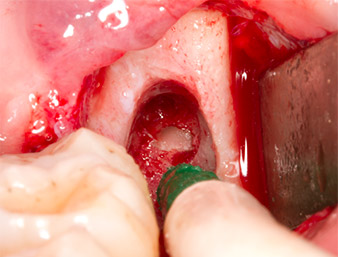

Using an instrument for periodontal debridement (Piezomed P1), the periodontal ligament space of the radix relicta was then widened minimally (Fig. 8).

The same activated instrument was inserted into the root canal and loosened the fragment as a result of its micro-oscillating vibrations (Fig. 9, 10).

Piezomed P1

Fig. 9: The Piezomed P1 instrument is recommended by the manufacturer primarily for periodontal debridement but is also suitable for surgical purposes. Here it is placed in the root canal after minimal widening of the periodontal ligament space.

Fig. 10: Due to its slender shape, the instrument can penetrate the root canal and remove the root remnant by means of micro-oscillation (vibration).

It was then possible to remove the approximately six-millimetre-long root remnant in one piece with the P1 attachment (Fig. 11).

Periapical inflamed tissue was also removed very carefully with a manual excavator. Fig. 12 shows the empty alveole with exposed inferior alveolar nerve.